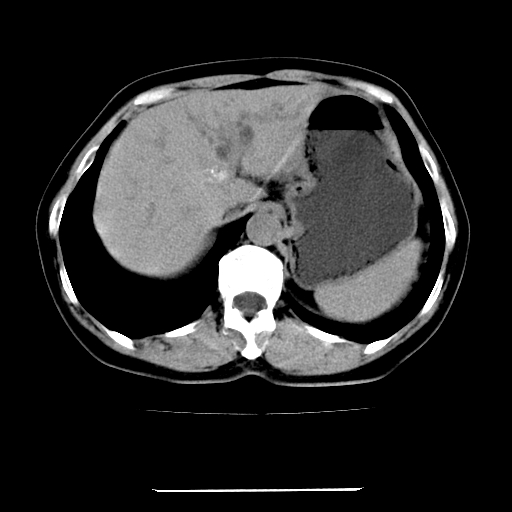

标题: CT22301:女,67岁,上腹部疼痛一周伴皮肤黄染,无发热。 [打印本页]

女,67岁,上腹部疼痛一周伴皮肤黄染,无发热。

左叶肝内胆管结石,并远端肝内胆管扩张。

考虑:肝内胆管结石继发肝内胆管扩张,右肾旋转不良。

肝内外胆管结石并肝内胆管扩张。

考虑胆管结石并左叶肝内胆管扩张。

肝内外胆管扩张,左叶胆管内结石

1、肝门高密度影下层面和胰头层面可见轻度胆管扩张,而静脉和延迟期均未见扫描完胰头,不能完全排除胰头占位。2、肝门部高密度影,考虑钙化或结石。

考虑肝门胆管癌伴门脉左支受侵包埋,建议mrcp进一步检查。